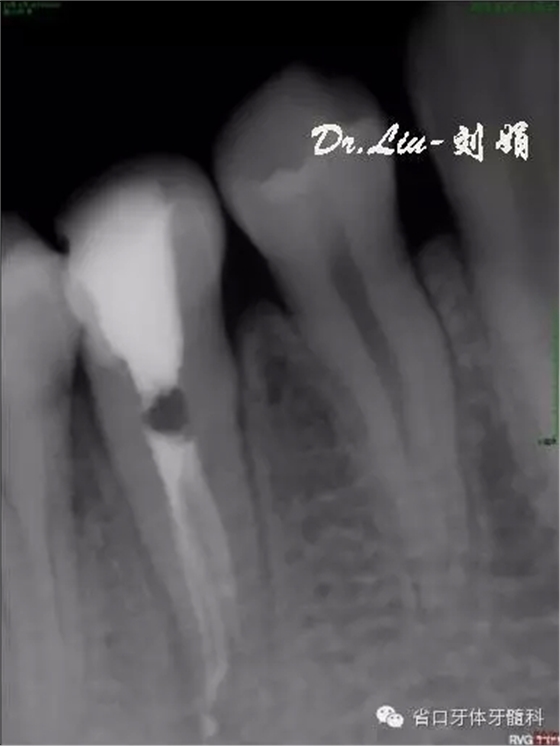

牙片顯示:45充填物至髓腔,根管內(nèi)無(wú)充填物影像,根管影像不清疑似多根管,根尖區(qū)見(jiàn)X線透射區(qū)。

圖1:術(shù)前X線片,根管影像不清,根尖區(qū)見(jiàn)X線透射區(qū)